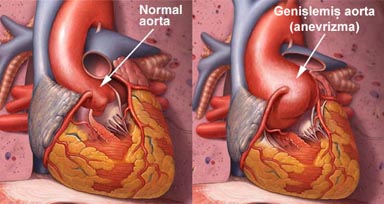

Anevrizma damarların kalıcı olarak genişlemesi veya balonlaşmasıdır. Anevrizma en sık vücudun en büyük atardamarı olan aortada gelişir. Anevrizma zamanla daha da genişler ve tedavi edilmediği takdirde patlar ve çoğunlukla ölüme neden olur. Çoğu kez anevrizmalar bir şikayete neden olmaz ve tesadüfen başka nedenlerle yapılan incelemelerde fark edilir Anevrizma erkenden teşhis edildiğinde kalıcı tedavisi mümkündür. Anevrizmanın klasik tedavisi ameliyat ile genişlemiş damar bölümünün suni bir damar ile değiştirilmesidir. Daha az rahatsızlık verebilecek bir başka tedavi yöntemi ise özel bazı kateterler ile damarın içine girilip, anevrizmanın olduğu damar bölümüne içerden suni damarın yerleştirilmesidir.

Anevrizma damarların kalıcı olarak genişlemesi veya balonlaşmasıdır. Anevrizma en sık vücudun en büyük atardamarı olan aortada gelişir. Anevrizma zamanla daha da genişler ve tedavi edilmediği takdirde patlar ve çoğunlukla ölüme neden olur. Çoğu kez anevrizmalar bir şikayete neden olmaz ve tesadüfen başka nedenlerle yapılan incelemelerde fark edilir Anevrizma erkenden teşhis edildiğinde kalıcı tedavisi mümkündür. Anevrizmanın klasik tedavisi ameliyat ile genişlemiş damar bölümünün suni bir damar ile değiştirilmesidir. Daha az rahatsızlık verebilecek bir başka tedavi yöntemi ise özel bazı kateterler ile damarın içine girilip, anevrizmanın olduğu damar bölümüne içerden suni damarın yerleştirilmesidir.

Anevrizma damarların kalıcı olarak genişlemesi veya balonlaşmasıdır. Anevrizma en sık vücudun en büyük atardamarı olan aortada gelişir. Anevrizma zamanla daha da genişler ve tedavi edilmediği takdirde patlar ve çoğunlukla ölüme neden olur. Anevrizmadan ölüm toplumda ölüm nedenleri arasında 13. sıradadır.

Anevrizmanın nedeni tam olarak anlaşılabilmiş değildir. Ancak damar duvarının içindeki kan basıncına dayanmasını sağlayan kollagen ve elastin isimli proteinlerin çok çeşitli nedenlerle tahrip olması anevrizmanın en belirgin özelliklerindendir. Yani anevrizmada bir çeşit damar duvarının zayıflaması ve sonra da içindeki basınca dayanamayıp genişlemesi söz konusudur. Bu olay sıklıkla ateroskleroz yani damar sertliği ile birliktedir.